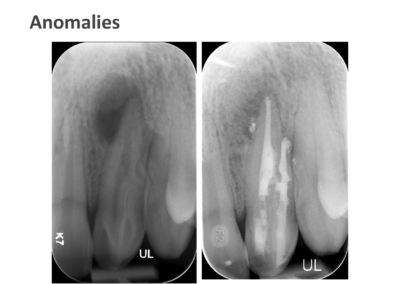

We take pride in providing the highest standard of care at ICE and believe that only the best is good enough for our patients. As such, Shakil completes all endodontic procedures using a state-of-the-art dental microscope. We accept referrals for consultations, root canal treatment (primary and retreatment), management of endodontic emergencies, dentoalveolar trauma and we are also happy to provide definitive restorations as required.